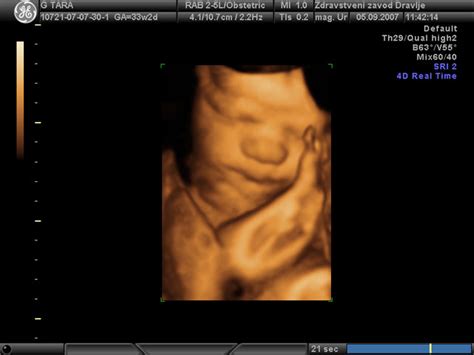

Ultrazvočne meritve: Le približna ocena

Med nosečnostjo ginekologi uporabljajo ultrazvok za oceno rasti in teže ploda. Vendar je pomembno vedeti, da so te meritve le približne. Zlasti v zadnjem trimesečju lahko odstopanja znašajo tudi do 10-15%, kar pomeni, da se lahko dejanska teža ob rojstvu razlikuje tudi za 500 gramov od ocenjene. Zato napovedi o teži otroka pred rojstvom niso stoodstotno zanesljive.